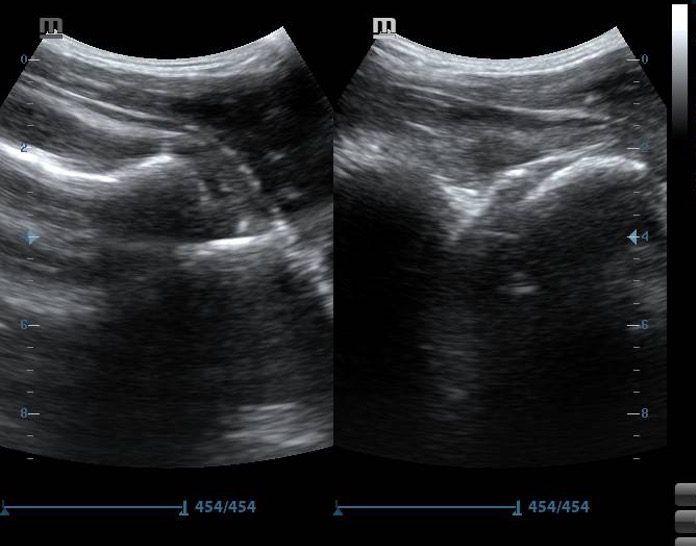

Figure 7. Pre-reduction (left) and post-reduction (right) images of right shoulder joint

The head of the humerus appears to be deeper in position compared to the glenoid rim on the first image. This indicates an anterior shoulder dislocation. The head of the humerus is in line with the glenoid rim in the image on the right, indicating successful reduction

Further confirmation of the reduction can be done by observing the head of the humerus on ultrasound while rotating the affected shoulder internally and externally with the arm adducted. The head will appear to move smoothly within the glenoid rim.